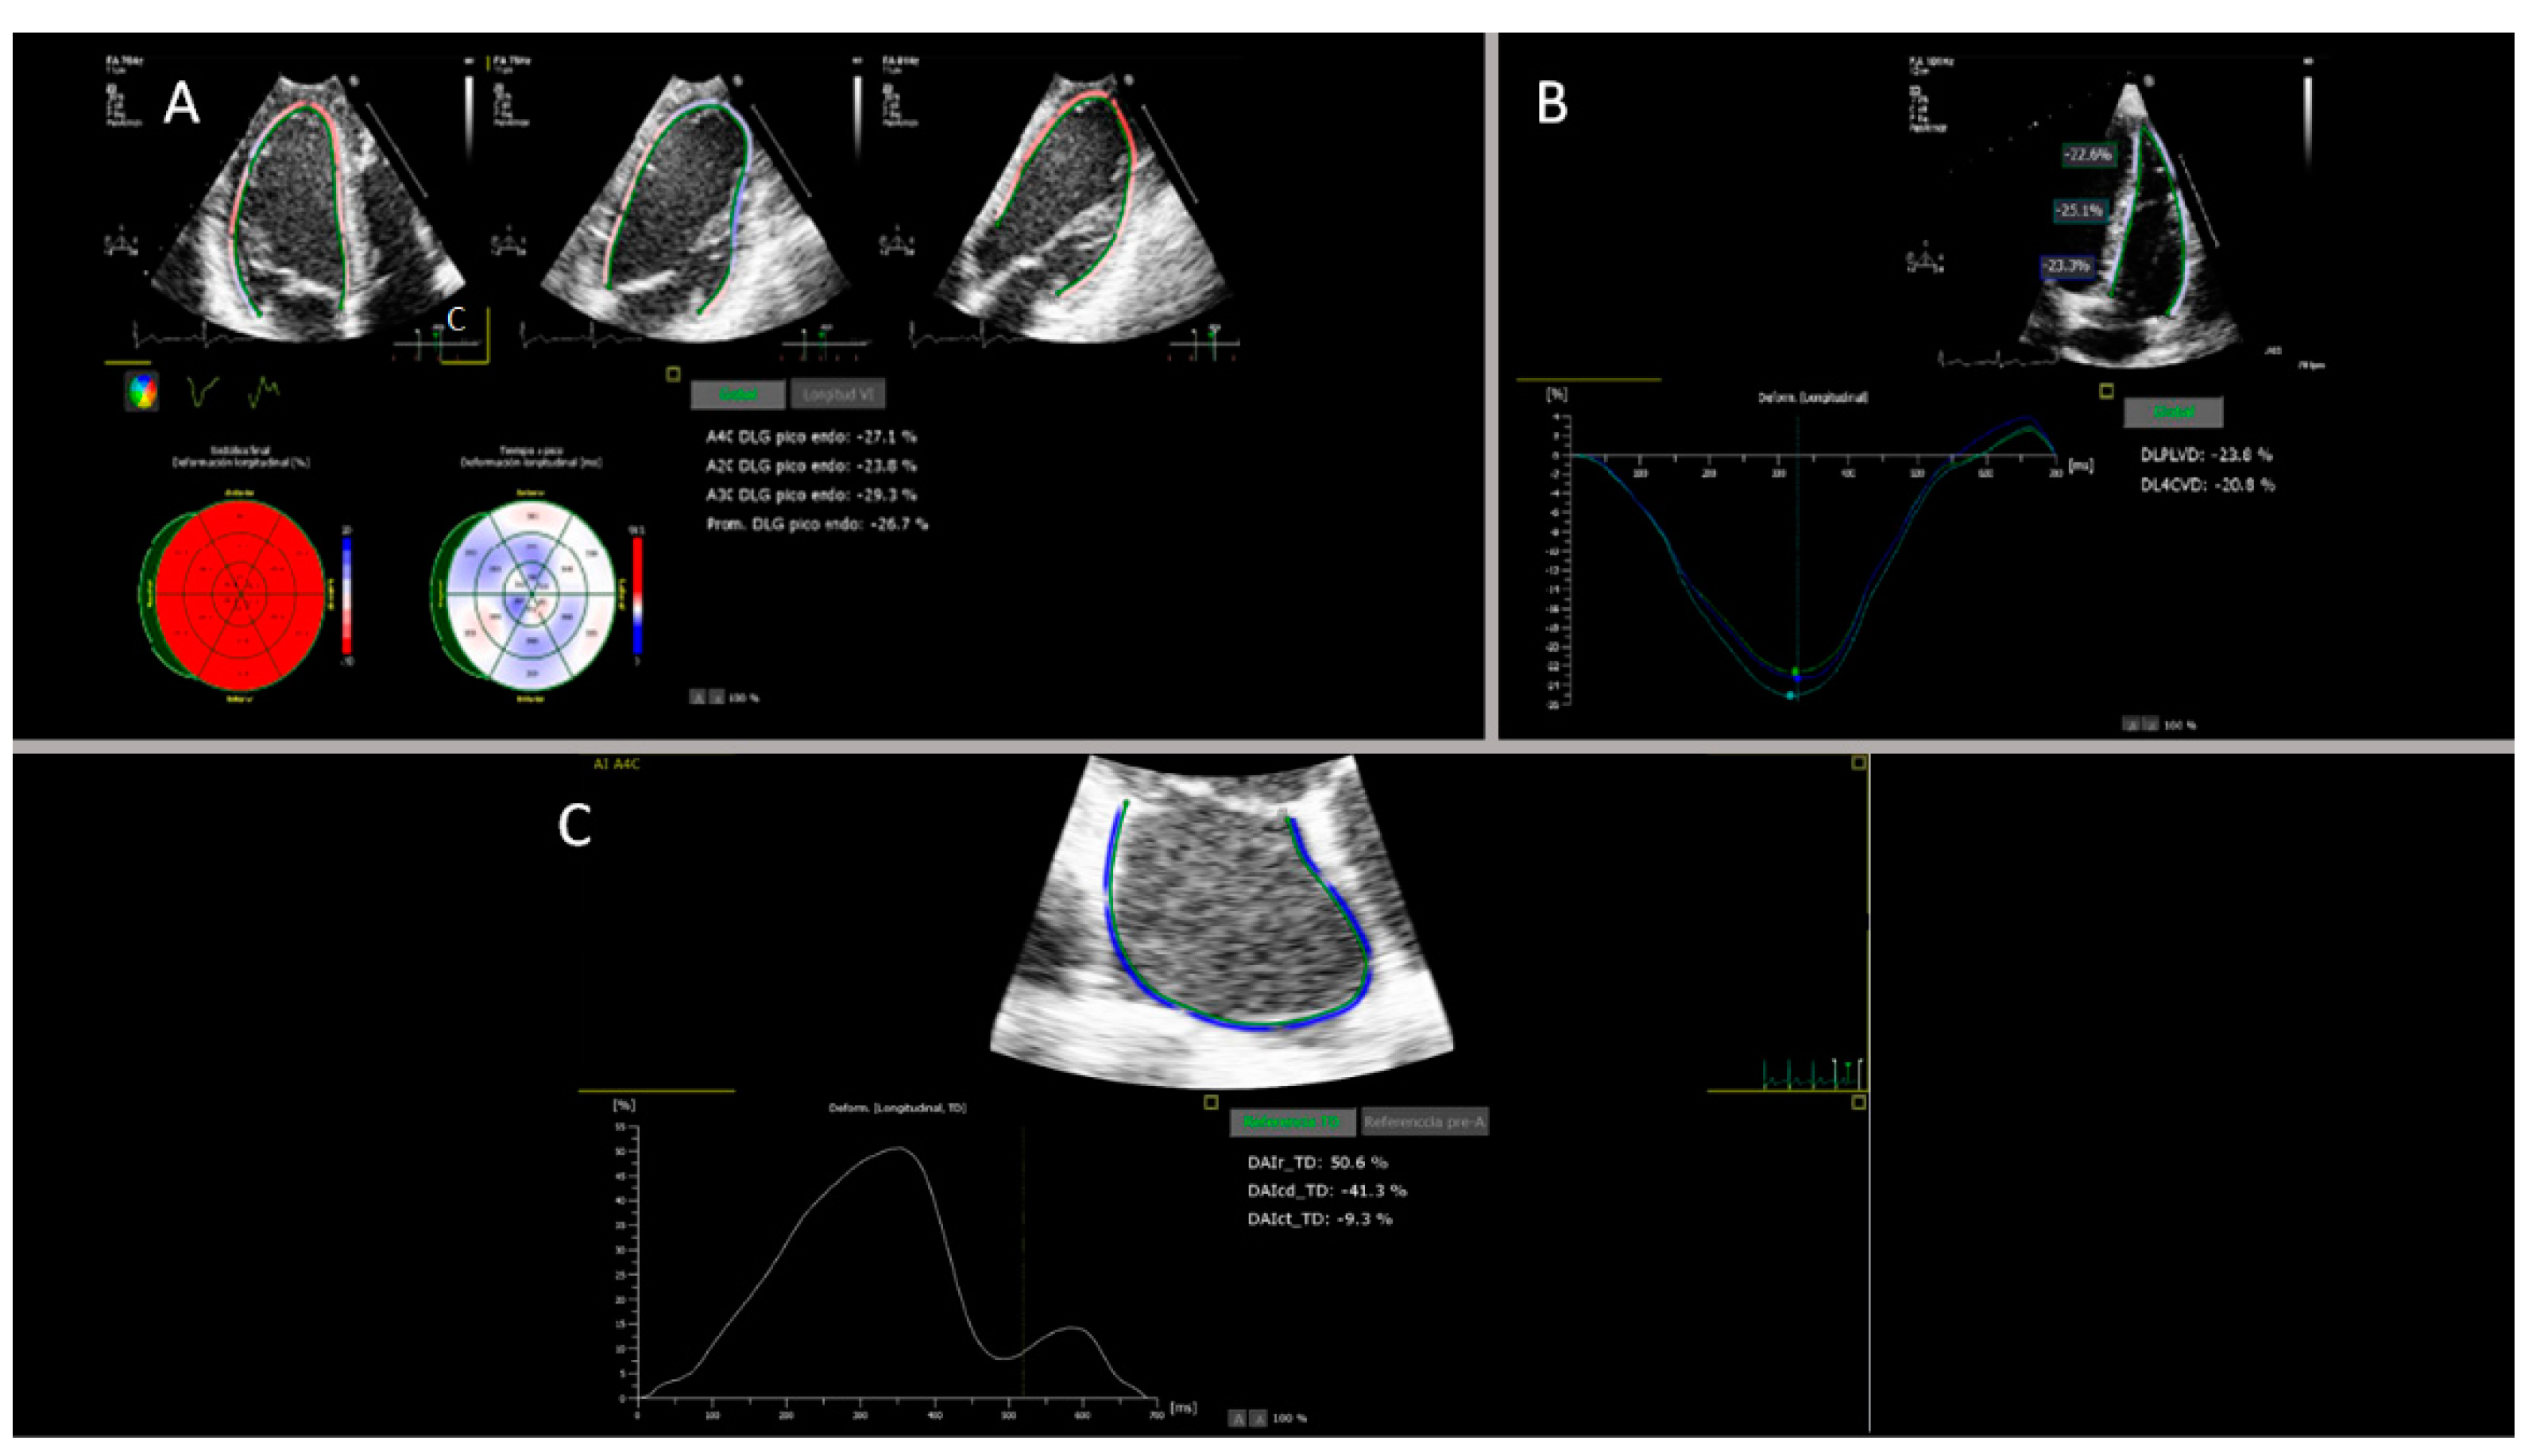

2.3. Strain Analysis